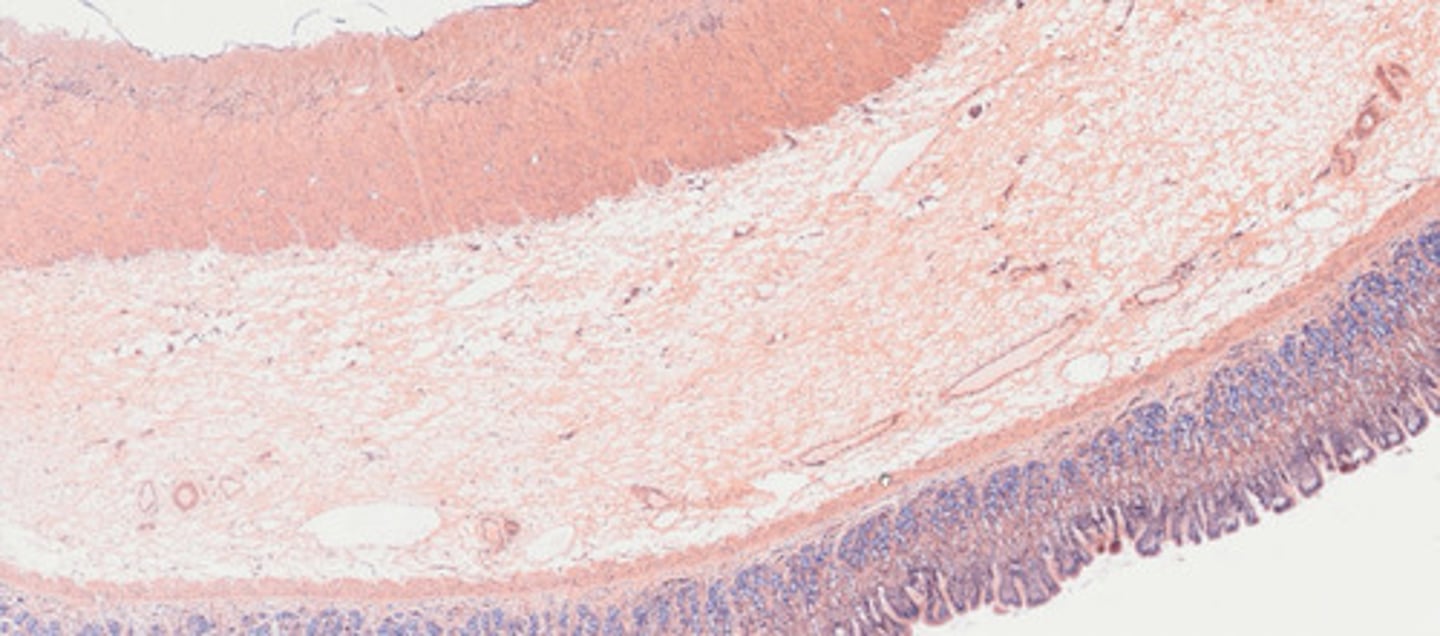

Moczowód (H+E)

Pęcherz moczowy (H+E)